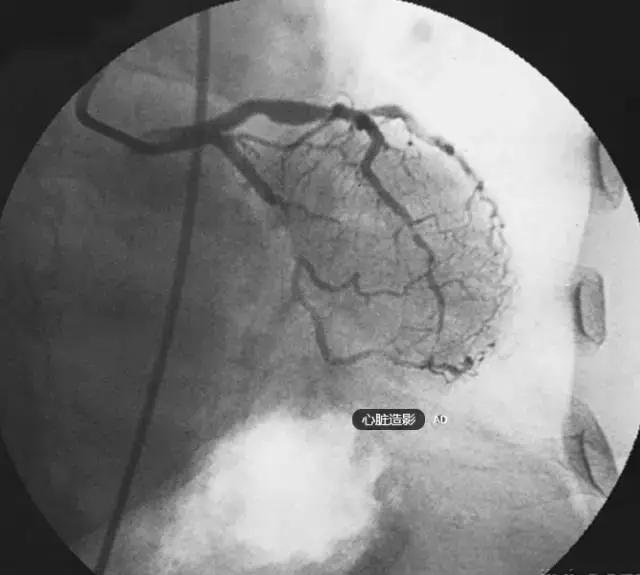

冠狀動脈造影簡稱冠脈造影,是使冠狀動脈在X線下顯影的方法。

冠狀動脈是供應心肌血液的血管,分為左、右冠狀動脈,分別直接開口于主動脈根部的左、右主動脈竇內(nèi),由此開始向心臟表面延伸并不斷分支進入心臟。

由于血液與血液壁是同樣不透光的,且與心臟重疊,所以血管腔內(nèi)發(fā)生有粥樣斑塊或狹窄時,在普通X光下是無法看出的,只有通過血管造影才能發(fā)現(xiàn)這些病變。

根據(jù)血管受阻的程度不同,冠心病的臨床表現(xiàn)有心絞痛、心肌梗死、心律失常、無癥狀性心肌缺血、甚至猝死等。冠狀動脈造影不僅可以確定冠狀動脈是否存在阻塞以及阻塞的嚴重程度,還可以為下一步的治療方案提供依據(jù)。